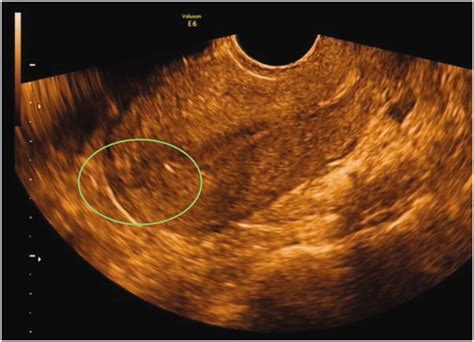

When a physician suspects a perforation, they will typically initiate a diagnostic process to determine the extent of the damage. Imaging technologies play a vital role here. A transvaginal ultrasound is often the first line of defense, as it can help locate an misplaced IUD or detect free fluid in the pelvic cavity that might indicate bleeding. In more complex scenarios, a CT scan or MRI may be required to visualize the abdominal cavity more clearly and rule out injury to the bowel, bladder, or major arteries.